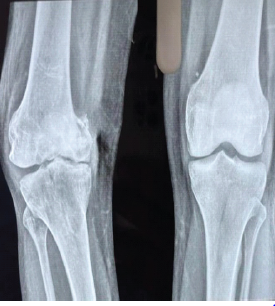

Isolated Double Hoffa Fracture of the Distal Femur without Intercondylar Extension: A Rare Case Report

Utkarsh Jain , Vipin Gupta , Navdeep Singh Keer